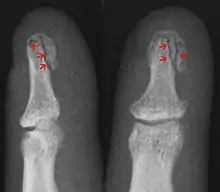

| Avulsion fracture | A fragment of bone is separated from the main mass (image shows a Busch fracture) | |||

| Comminuted fracture | The bone is shattered | often from crushing injuries[34] |